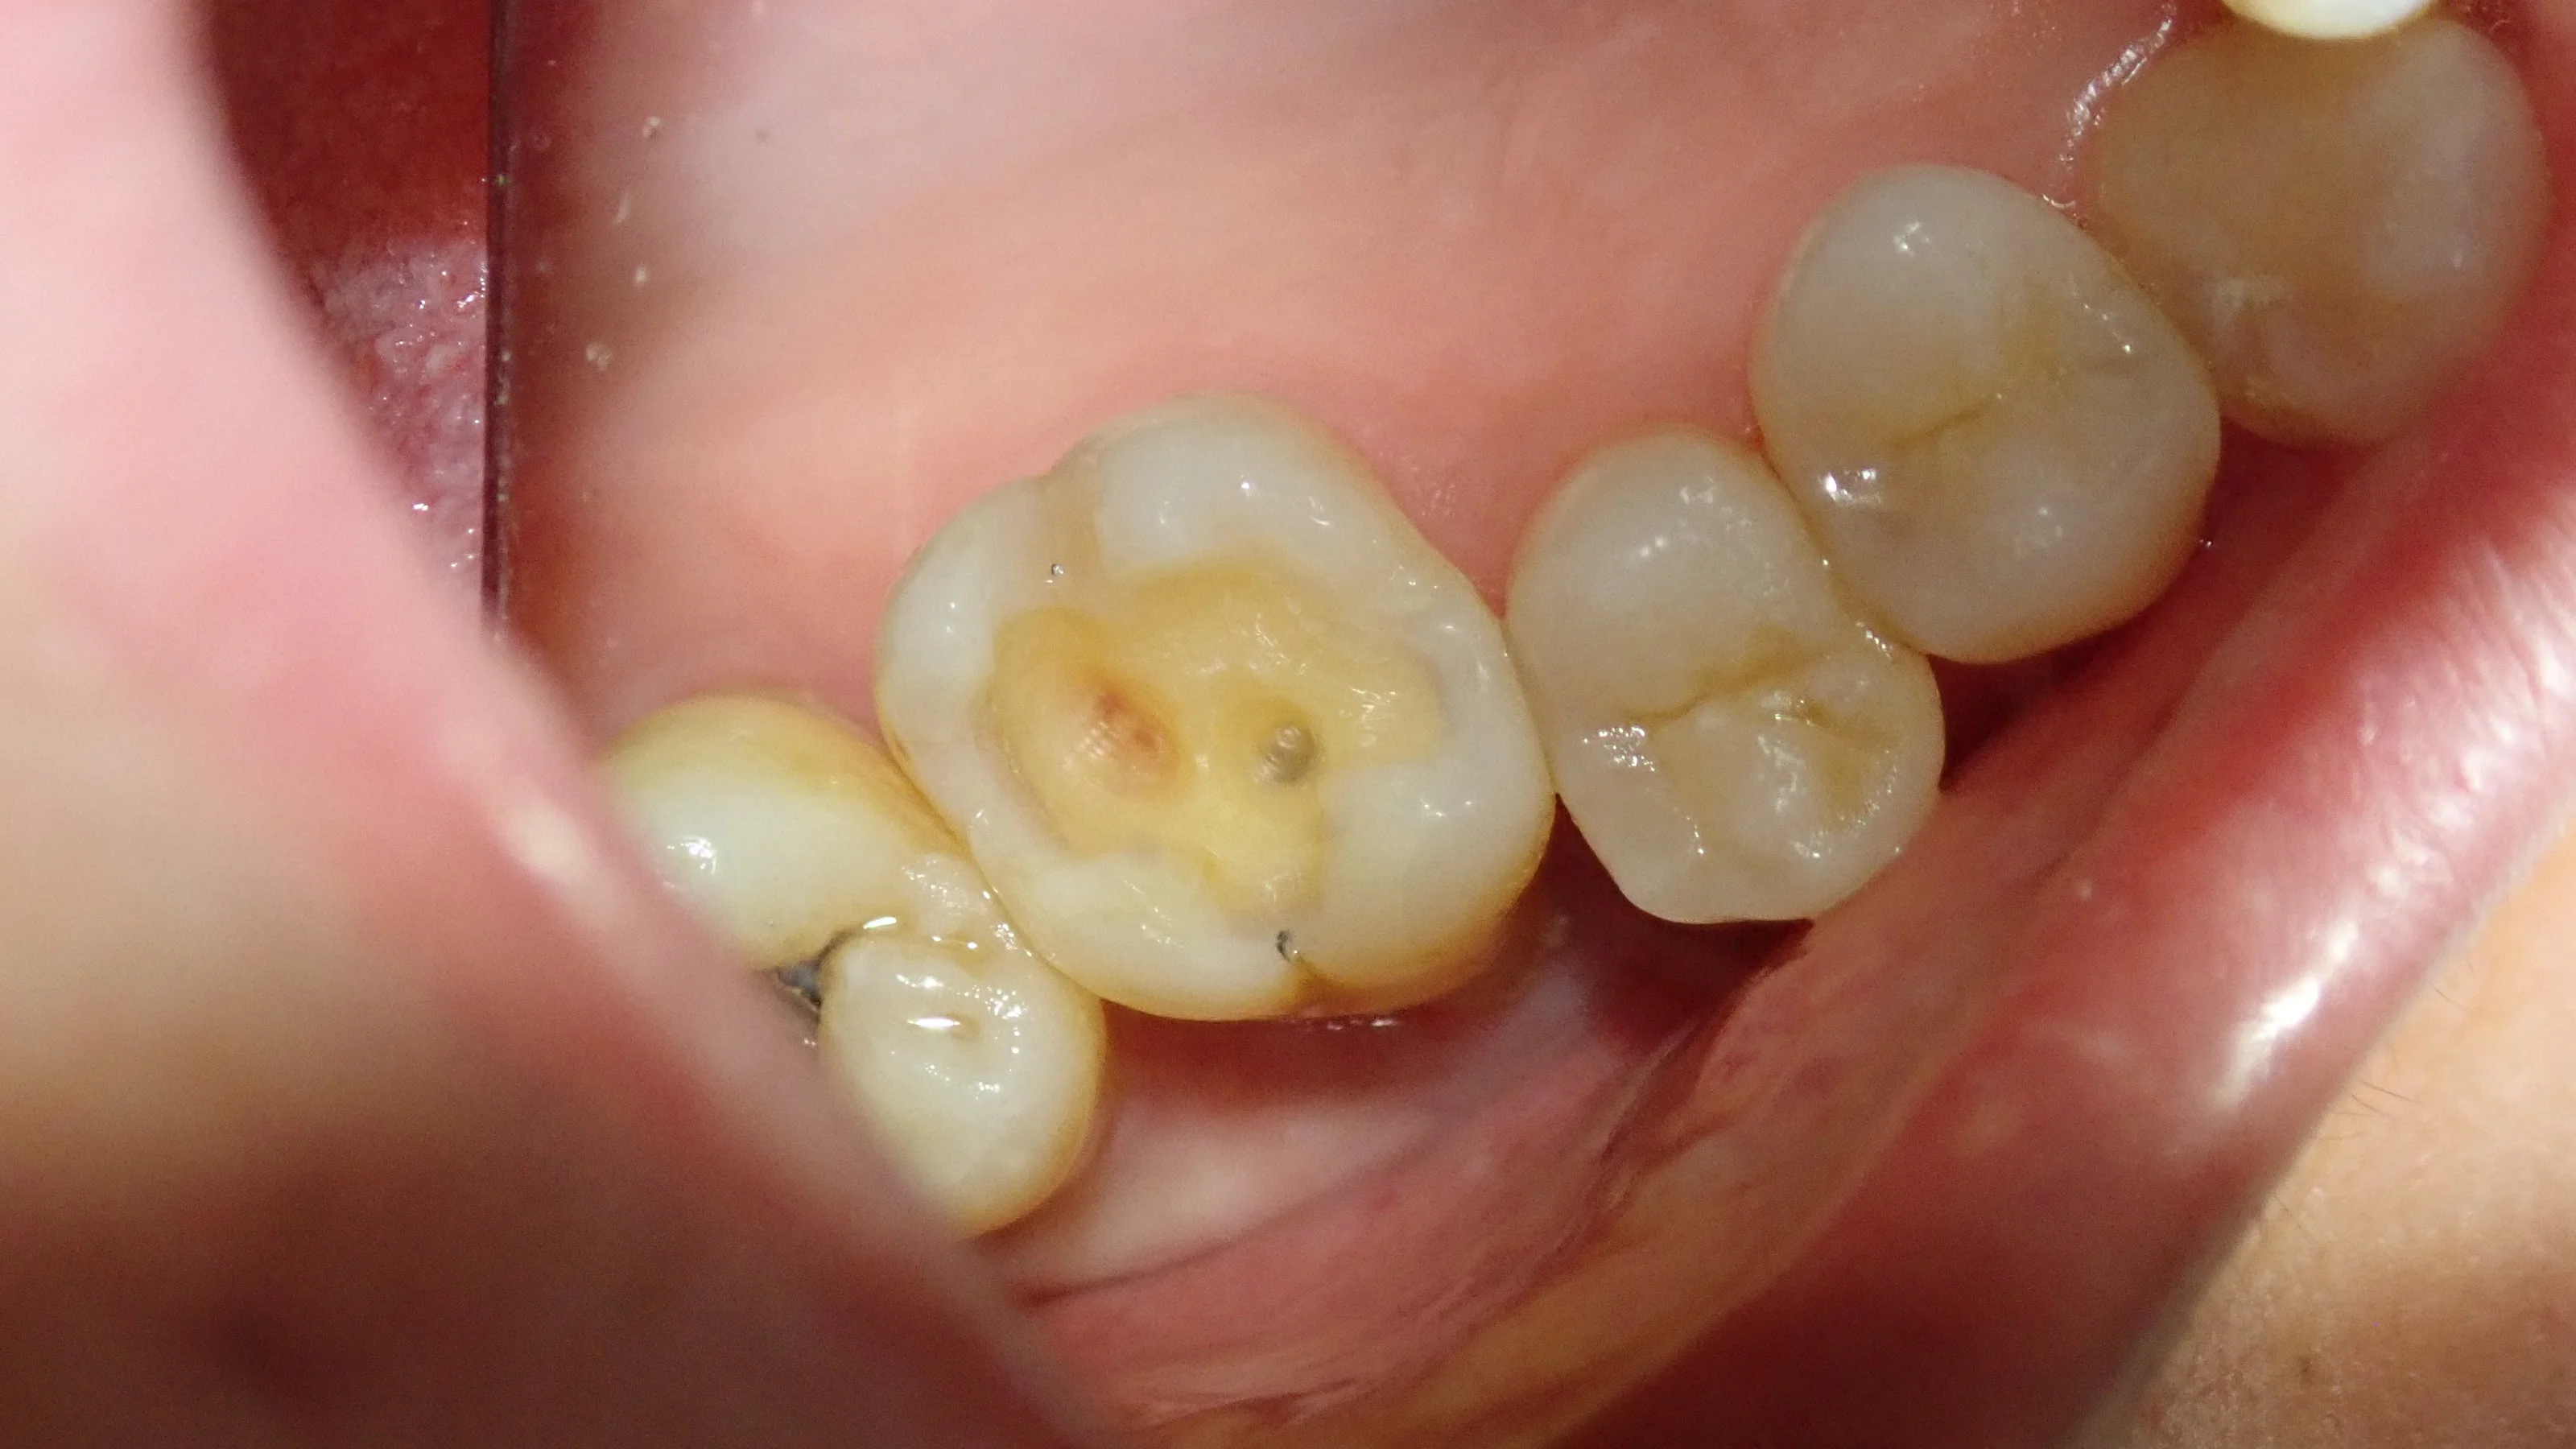

さて、そこら辺の古い材料を取り除いたのがこちらです。

この画像だと深さが分かりづらいですが・・・

普通に神経がちょっと近い状況になっていました。

色がついているところは虫歯ではなく、着色しているだけの状況ですので、全く問題はありません。